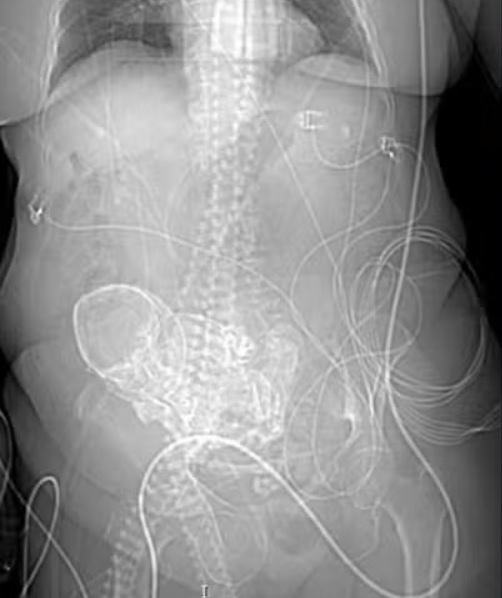

Depois de uma bateria de exames, o hospital informou que "foi detectada uma condição rara chamada de litopédio", durante um exame de imagem. Foto: Imagem de Roman Paroubek por Pixabay -

Litopédio se caracteriza pelo óbito de um feto durante a gravidez, seguido pela calcificação dele dentro do abdômen da mulher. Foto: reprodução -

A equipe médica desconfiou que o "bebê de pedra" estava na barriga da idosa há pelo menos 56 anos, que foi quando ela ficou grávida pela última vez. Foto: Daniel Reche por Pixabay -

“A partir da infecção constatada, equipe médica da Unidade de Terapia Intensiva (UTI) decidiu pela realização cirúrgica de emergência, com a finalidade de remover o feto e controlar o processo infeccioso”, comunicou a instituição, em nota. Foto: insung yoon Unsplash -

O hospital explicou que a cirurgia foi feita para tentar salvar a vida da mulher, pois ela estava com sepse, uma condição grave causada por uma infecção que se espalha pelo corpo. Foto: Piron Guillaume Unsplash -